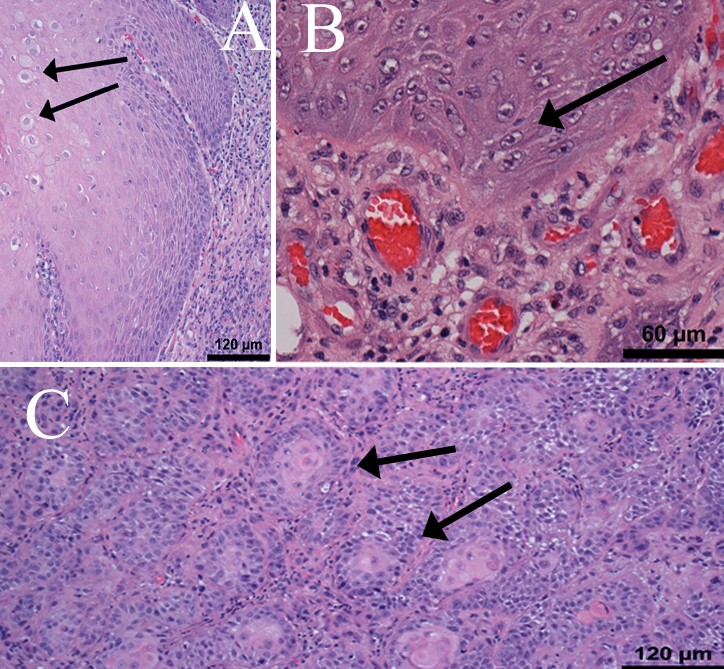

penile cancer photos download

Posts: penile cancer photos download